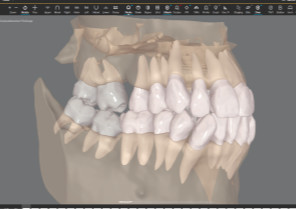

Maximizes the efficiency of powerful ClinCheck tools like 3D Controls.

Four views in one integrated platform to enhance treatment planning.

Roots with semitransparent bone

Roots with semitransparent bone